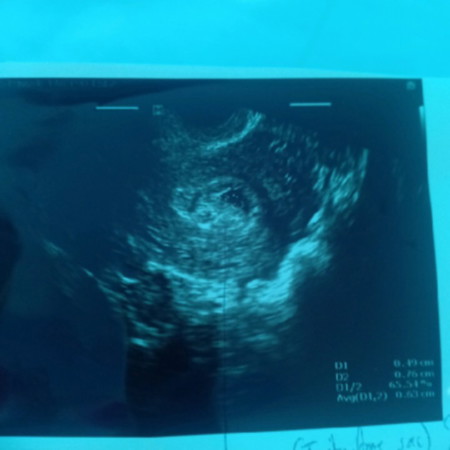

หาถุงตั้งครรภ์ไม่เจอ

หมอนับจากประจำเดือนวันแรกครั่งสุดท้าย 7 สัปดาห์ ซาวไม่เจออะไรในมดลูก. เจอจุดหรือถุงเล็กๆ. เล็กมากหมอไม่แน่ใจว่าถุงตั้งครรภ์รึเปล่า. ขนาดและรูปร่างไม่สวย รอผลเลือดเทียบกัน48ชั่วโมง อาจจะท้องนอกมดลูก หรือไม่ก็ท้องลม. อีกและ พูดแบบนี้อีกและ. แม่เครียดจนไมเกรนขึ้นเลยจ้า. ไปแอบไปซ่อนอยู่หนายย. แม่ร้องไห้จนตาบวมแล้วลูกเอ้ย?

อัพเดตคะ 7 week 1 d น้องโตตามเกณฑ์ดีคะ ถุงน้ำเล็กๆ ก็ไม่เจอคะ เห็นถุงไข่แดงกับหัวใจน้องกระพริบคะ